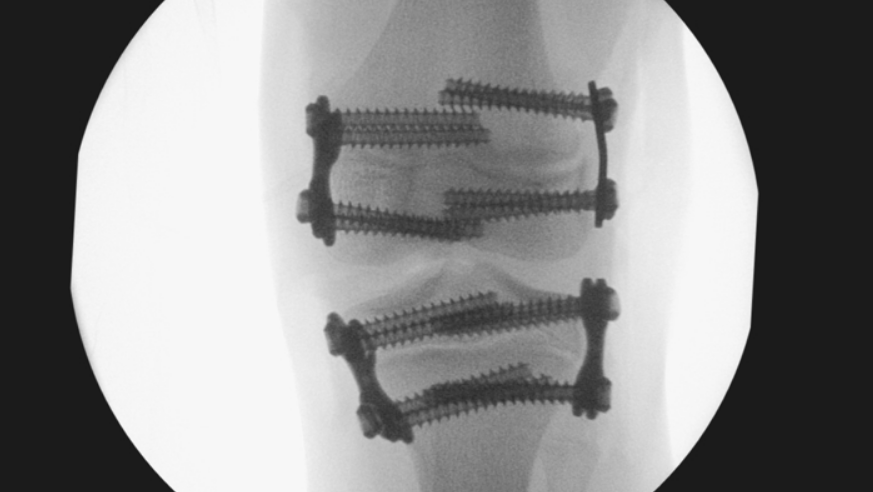

It raised concerns that surgeries were carried out on Amy's knees when she was nine, and her legs were still growing.

But the assessment said metal plates inserted into her longer leg to stop it growing were too big, causing pain and requiring replacement.

Reviewers said the plates used to prevent bone growth in Amy's left knee were too big and not positioned correctly

Amy's right leg was then allowed to grow too much and ended up 3cm longer than her left.